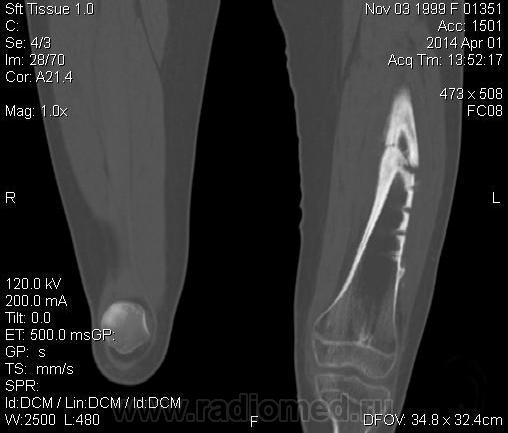

Молодая дама (14 лет) с переломом срдней трети диафиза левого бедра в анамнезе (декабрь 2012 г). Ломала ногу несколько раз в этом месте. Сейчас состояние после МОС. Как следует понимать изменения в кости, формируется ли ложный сустав?

Похоже ложный сустав сформировался. Но при нём обычно большие напластования костной мозоли, здесь их нет. В таких случаях смотрю при скопии подвижность.

Ох, не хочется думать о ложном суставе в 14 лет... По срокам под ложный сустав подходит, он характеризуется замыканием костномозгового канала с формированием подобий суставных поверхностей. У нее же есть хиленькая периостальная костная мозоль по задней поверхности бедра удерживающая отломки в правильном положении. Я склонна думать, что это скорее застарелый перелом (оно же замедленная консолидация). Здесь очень важно посмотреть предыдущие снимки (поиск рефрактуры, либо отсутствия полной консолидации).

Настоящего, родного ложного сустава пока нет, хотя костномозговой канал дистального отломка уже закрыт - образовалась склерозированная замыкательная пластина. Варусная деформация почти в 165 градусов... Я бы заключилась неполной консолидацией и варусной деформацией, прогностически формирование ложного сустава очень вероятно.